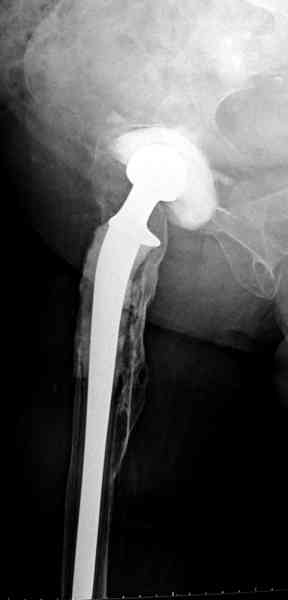

Приглашенный хирург установил ревизионный вариант бедренного компонента без замены ацетабулярного компонента, что осложнилось нагноением и свищами на уровне сустава и средней трети бедра. После двухгодичного безуспешного лечения перевязками и антибиотиками больная обратилась к нам на консультацию.

Повторная операция по удалению тотального протеза с irrigation&debridment, канал после очистки цемента обильно промыт и рассверлен римером.

Приготовлен цемент из расчета: Tobramycin 2.4 g (2 флакона), Vancomycin 2 млн (4 флакона) и 2 упаковки цемента с добавлением дополнительного флакона цементной жидкости.

После обработки ацетабулярного компонента, ещё в мягком цементе в полости вертлужной впадины головкой бедренного компонента сделана выемка для головки, чтобы свежий цемент не прилипал к головке. Головку бедренного компонента завернул обычной стерильной фольгой, которую после образования выемки отлепил от головки.

Для спейсера в бедро использовал старый длинный бедренний компонент меньшего диаметра, облепленный со всех сторон цементом с антибиотиком.

№3-6 снимки с осложнением